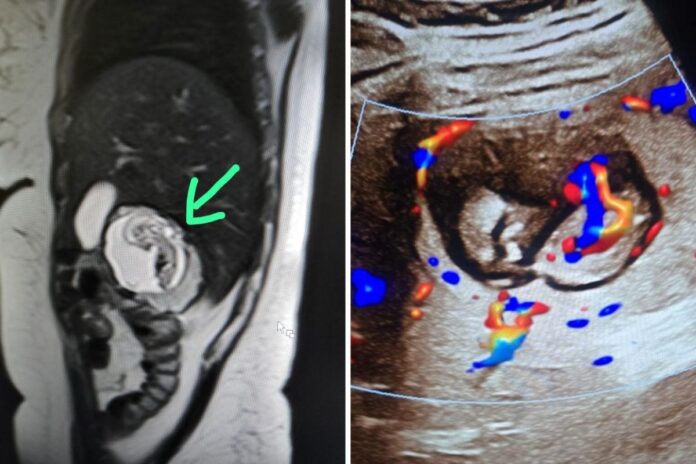

UP Woman’s Foetus Growing In Liver, Not Uterus: Only 8 such cases reported worldwide. Meerut doctors say this could be India’s first intrahepatic ectopic pregnancy